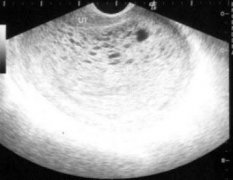

妇科常规检查主要是对一些妇科炎症疾病作早期预防和早期治疗。普通的妇科检查项目包括:外阴、阴道、宫颈、输卵管、卵巢的检查、白带常规的检查、阴道式B超检查、宫颈刮片检查、乳腺检查。

2、检查的项目。一般的妇科检查主要是包括全身检查、腹部检查以及盆腔检查。检查外阴、阴道、子宫颈和子宫、输卵管、卵巢、宫旁组织以及骨盆腔内壁的情况。有的女性因身体原因还会选择一些特殊检查,其费用自然会高一些。